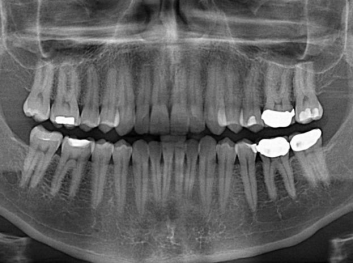

哈佛大學:新型生物材料讓牙齒再生 來源: 南京泰盛生物科技有限公司 發(fā)布時間:2018-04-10

損壞的牙齒如何自我修復?近日,來自哈佛大學和諾丁漢大學的研究人員研發(fā)了能夠刺激牙齒干細胞再生的新型生物材料,而這種新材料研發(fā)成功的背后,正源于他們對牙齒如何實現(xiàn)自我修復這個課題的不斷探索。

據(jù)美國期刊《大眾科學(Popular Science)》報道,此種新型生物材料,不僅可以有效地取代傳統(tǒng)補牙填充物,刺激牙齒干細胞再生,患者也有望無需再接受根管治療,使蛀牙患者免除牙根感染或牙髓壞死的苦惱,一個全新的牙齒治療時代即將來臨。

Adam Celiz,是來自諾丁漢大學的研究人員,他和同事開發(fā)的這種新型合成生物材料,能刺激干細胞在牙髓部的生長。與普通材料一樣,這種合成材料被填充到牙齒并用UV光硬化。

在體外測試中,材料刺激干細胞進入牙本質(zhì)的增殖和分化速度,促進形成牙齒骨組織。研究人員認為,一旦材料在受損牙齒中應用,這些干細胞可以自動修復來自填充物上的損壞。在本質(zhì)上,該生物材料將使牙齒自愈。

在未來,Adam Celiz說,可再生材料能制成各種填充物以便受損牙齒的自身治愈,降低補牙失敗率,甚至會消除大部分人對根管治療的需要。